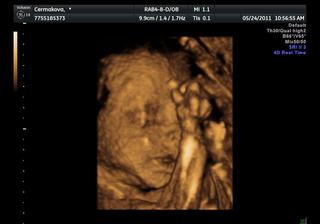

Na 3D měla pořád packy před obličejem, fotky nejsou až tak zdařilé, videa jsou některá pěkná, ale sem nejdou bohužel vložit..

@suzamen i na té fotce je krásně vidět, moc držím palečky, aby vše bylo jak má a v zimě ses dočkala zdravého miminka